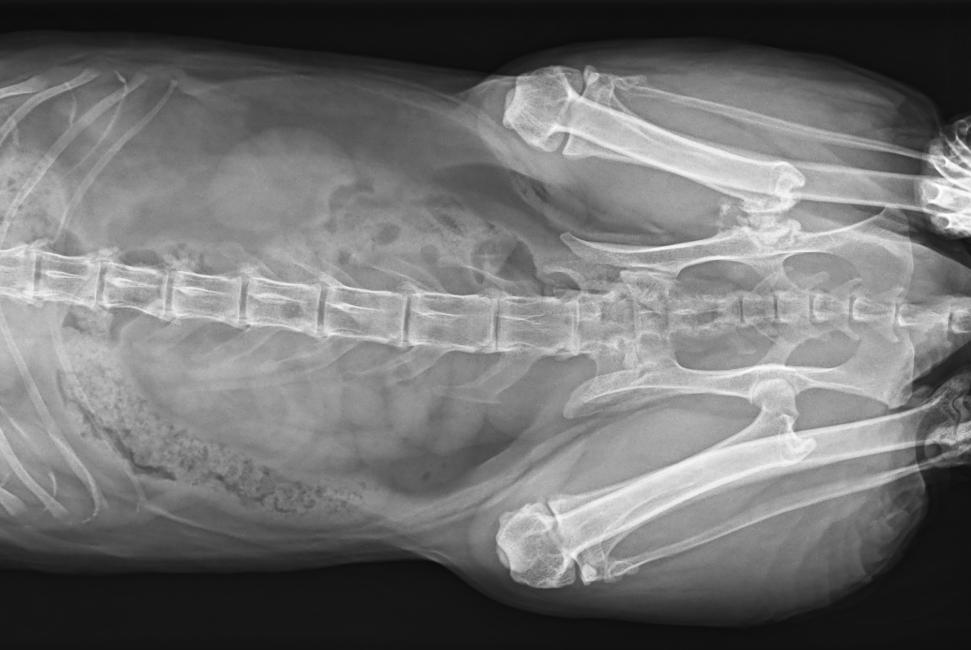

● 17*17大尺寸平板探測(cè)器,獲得高質(zhì)量圖像

● 優(yōu)異的空間分辨率及信噪比,提升圖像質(zhì)量

● 采用線噪聲消除技術(shù),使成像質(zhì)量提升40%

● 智能高效的圖像處理軟件,大幅提升圖像質(zhì)量